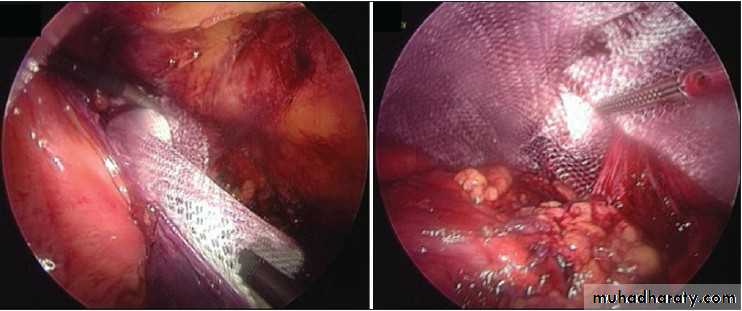

Obturator HerniaOperative Approach

• REPAIR• Simple closure of the hernial defect with one or more interrupted sutures

• Plugging the canal with cartilage, free omentum ,obturator fascia, polypropylene mesh, teflonpatch, or bladder wall.

• Recurrence – 10% for simple closure

Intraoperative image showing left sided obturator hernia within white outline and incidental femoral hernia at 11’o clock position.

Noel P. Lynch et al. J. surg. case rep. 2013;2013:rjt050